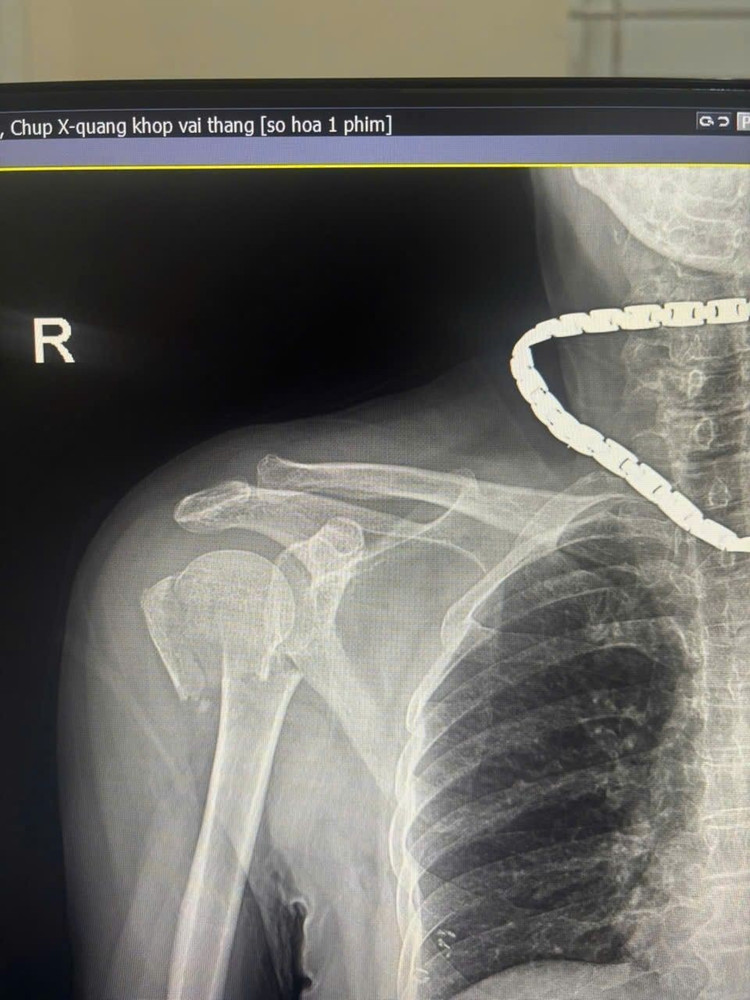

Hình ảnh gãy xương cánh tay trên phim chụp - Ảnh BVCC

Trước đó, bệnh nhân bị ngã được đưa vào viện trong tình trạng đau nhiều vùng vai phải, hạn chế vận động. Qua thăm khám lâm sàng và chẩn đoán hình ảnh, người bệnh được xác định gãy kín đầu trên xương cánh tay phải và được chỉ định phẫu thuật kết hợp xương bằng nẹp vít khóa.